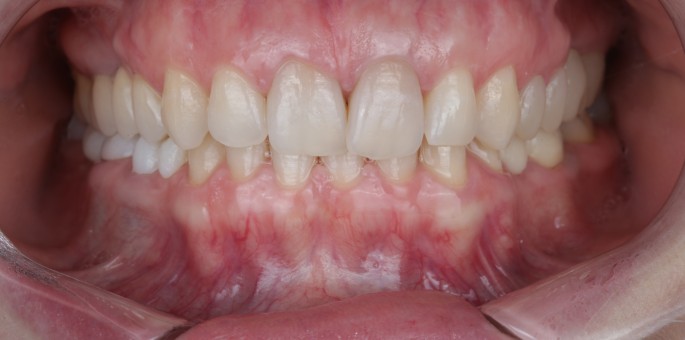

Pacient în vârstă de 42 de ani, cu fracturi dentare extensive pe dinții frontali în urma unui accident, necesitând restaurări complete în zona estetică.

Rezultatul Estetic

Restaurare completă în 4 săptămâni:

• Aspect natural identic cu dinÈ›ii originali

• FuncÈ›ie masticatorie completă

• Rezistență optimă la uzură È™i fractură

• Integrare perfectă cu gingia

• SatisfacÈ›ie estetică È™i funcÈ›ională maximă

Pacientul a revenit la încrederea în sine și nu mai ezită să zâmbească în public.